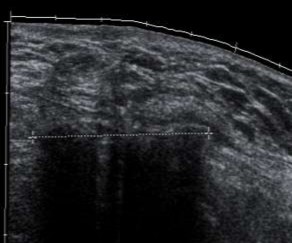

3.7.1. Kết quả siêu âm hình ảnh học của vùng bẹn sau khi đặt tấm lưới nhân tạo

Hình 3.1. Hình ảnh siêu âm mô xơ ở vùng bẹn phải, xuất hiện đường tăng âm với bóng đen cản âm ở phía sau. Bệnh nhân: Ngô Tá Tr 69 tuổi, Nam.

Hình 3.2. Hình ảnh siêu âm mô xơ ở vùng bẹn trái, xuất hiện đường tăng âm với bóng đen cản âm ở phía sau. Bệnh nhân: Phan Văn S. 59 tuổi, Nam.

Hình 3.3. Hình ảnh siêu âm mô xơ ở vùng bẹn phải, xuất hiện đường tăng âm với bóng đen cản âm ở phía sau. Bệnh nhân: Lê Nh. 67 tuổi, Nam.

Bảng 3.27. Phân bố độ dày mô xơ của tấm lưới dưới siêu âm

Số trường hợp | Tỉ lệ (%) | |

Mô xơ dày | 121 | 100 |

Mô xơ mỏng | 0 | 0 |

Tổng | 121 | 100 |

Độ dày mô xơ | 2,51 ± 0,21 mm | 2,1 - 3,5 mm |

Bảng 3.28. Phân bố vị trí tấm lưới dưới siêu âm

Nằm ngay ống bẹn | 121 | 100 |

Di lệch, di chuyển | 0 | 0 |

Mô xơ tạo thành quanh tấm lưới nằm ở vùng bẹn 100%, không có di chuyển và di lệch.